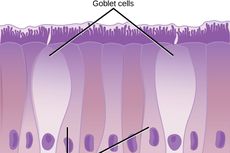

Sel-sel epitel tersusun rapat dengan tidak adanya ruang antarsel untuk membentuk penghalang atau pelindung bagi tubuh kita.

Jaringan epitel adalah salah satu jaringan dasar yang dibentuk dari kumpulan sel-sel, tersusun rapat, yang dibatasi oleh substansia interselularis